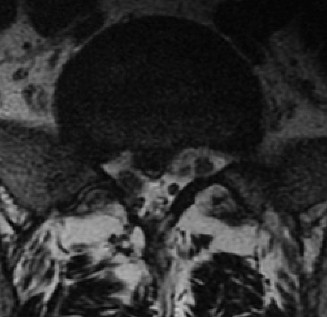

CASE 1 A 63-year-old male sustained a hyperextension injury to his neck while diving into a pool. Upon presentation, he reports decreased sensation in his hands and decreased strength in his arms and wrists, but no lower extremity complaints. On motor examination, he has 5/5 strength in his deltoids and elbow flexors and 4/5 strength in the elbow extensors, wrist extensors, and finger flexors. Lower extremity motor examination is normal. Sensation is decreased to light touch in both hands. Otherwise his sensation is preserved. Images of his cervical spine are shown in Figures 1–1 to 1–3.

Figure 1–2

The correct answer is (B). The clinical scenario describes a patient with central cord syndrome (CCS). CCS continues to be the most common incomplete spinal cord injury accounting for 15.7% to 25% of all spinal cord injuries. The characteristic presentation is an extension moment injury in a previously spondylotic and stenotic spine. Figures 1–1 to 1–3 demonstrate a spondylotic spine with central narrowing and CSF effacement that is worst at the C3–4 level. Bleeding, edema, and/or Wallerian degeneration lead to damage of the lateral corticospinal tract which is the main descending motor tract in the spinal cord. The more central anatomic position of the homunculus to the upper extremities places them at greater risk than those to the lower extremities. As such, injury to the lateral corticospinal tract is characterized by upper more than lower extremity involvement and motor deficits being more pronounced than sensory deficits.